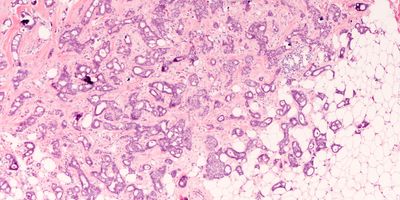

A multicenter study compared the analyses of cancer screening sample slides from digital pathology with light microscopy